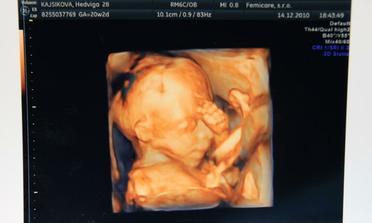

14.12.2010 dnes sme boli na morfologickom utz. ,všetko je v poriadku,len malinké sa akosi hambí,ešte aj nožičky prekrížilo. Pán dr. musel do neho štuchať lebo ani za nič na svete sa nechcelo otočiť a ukazoval nám ritku :°) Štuchal mi do bruška a malé sa len pomrvilo a to bolo všetko. Dr. povedal,že už od malička taký tvrdohlavý. A ručičky pred tváričku sa nás hambil. Aj 3D foto nám pán dr. dal :°) 20+2tt